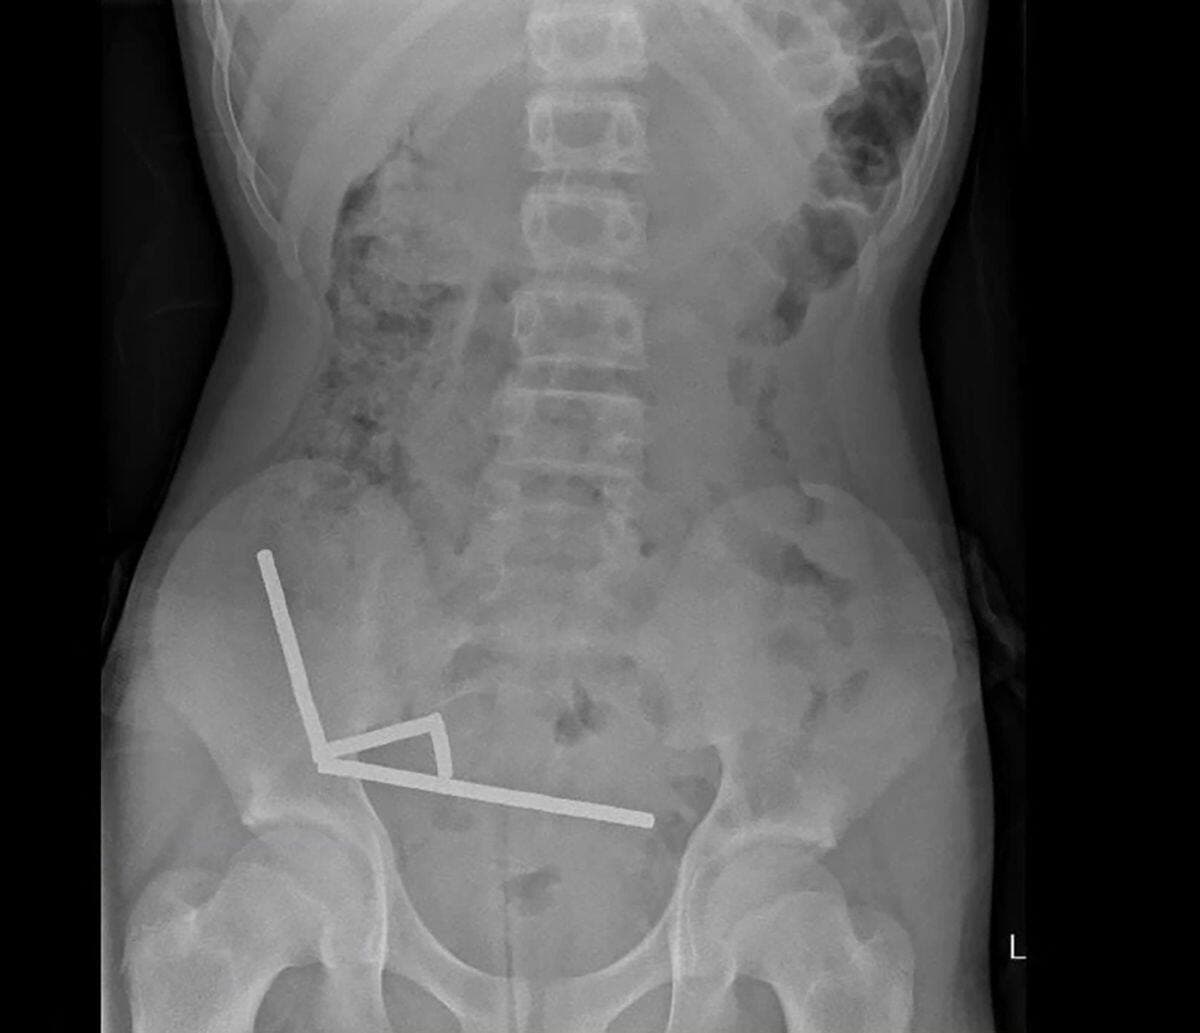

L'adolescent a été opéré et s'est vu retirer plusieurs parties nécrosées de ses intestins après avoir ingéré entre 80 et 100 aimants puissants au néodyme, de 5x2mm environ, une semaine plus tôt, avait expliqué la revue médicale. Il a pu rentrer chez lui depuis.